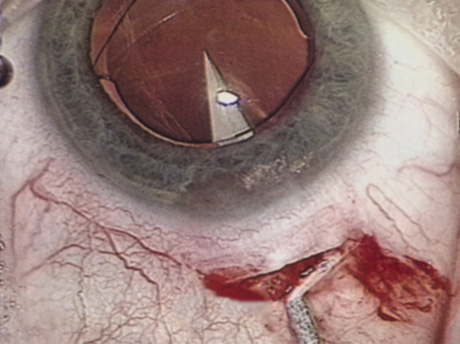

A mature cataract precludes visualization of the fundus. A B-scan ultrasonographic examination provides a real-time, two-dimensional (2D), cross-sectional image of the globe along the marked axis of the probe (Fig. 3). Cataracts are more common in patients with chronic retinal detachment, prior trauma, or intraocular tumors; therefore, a B-scan study is helpful in excluding structural posterior segment pathology before surgery on a mature cataract. Although a negative result to B-scan evaluation is reassuring, the surgeon should remember that it does not predict postoperative visual outcome. The B-scan can be thought of as a picture of Cincinnati from an airplane; the office buildings may all be standing, but you cannot tell whether the people in them are working.

Fig. 3. This B-scan ultrasound shows a normal looking posterior pole, without retinal detachment or intraocular mass. The vitreous cavity is echo lucent.